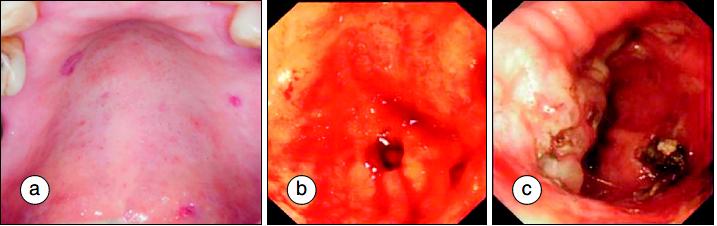

几乎所有SSc病人都有胃肠道受累。但有症状的不到一半。主要的症状有:吞咽困难、食管梗阻、烧心、声音嘶哑、吞咽后咳嗽;也可以带来腹胀、便秘和腹泻交替、假性梗阻、吸收不良等。口咽部粘膜血管扩张、胃窦血管扩张会带来慢性胃肠道出血,这是贫血原因之一。

上颚出血a;胃窦血管扩张,即西瓜胃b;西瓜胃予等离子光凝治疗后c, 参考2